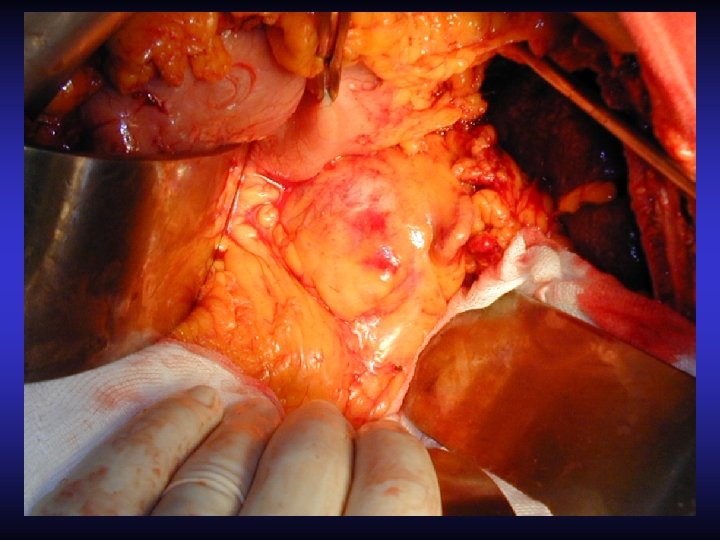

Resezioni parziali